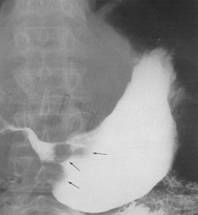

Semnele directe Nisa - imagine de plus de substanta de contrast, corespunzatoare escavatiei peretelui gastric. Din profil imaginea iese din conturul ipotetic al stomacului

Are o forma rotund - ovalara si este dispusa, de obicei, perpendicular.Marimea nisei este variabila, De cele mai multe ori, nisa se localizeaza la nivelul micii curburi în vecinatatea unghiului gastric, dar o putem întâlni si la nivelul micii curburi orizontale, a marii curburi, precum si la nivelul fetelor.

În jurul nisei, exista o reactie inflamatorie edematoasa care se vizualizeaza ca o linie lacunara - linia Hampton bine delimitata, având o grosime uniforma (gulerul ulcerului).

Incizura controlaterala reprezinta un spasm al musculaturii circulare care apropie marea curbura de mica curbura. Initial intermitenta, devine ulterior permanenta prin formarea, la acest nivel, a unui tesut fibros cicatricial, realizând o stenoza gastrica excentrica care biloculeaza asimetric stomacul (semnul indicatorului).

Gastrita hipertrofica acompaniaza leziunile principale. Poate fi localizata segmentar, în apropierea nisei, sau generalizata la întreg stomacul. În evolutia spre vindecare, pliurile devin convergente spre nisa realizând o imagine stelata.